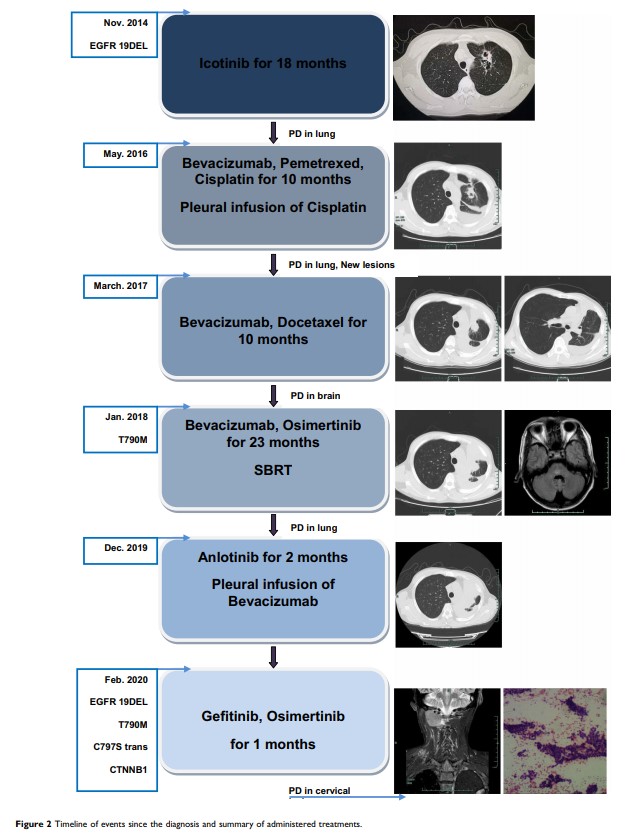

携带 EGFR 19Del/T790M/C797S 反式突变且同时伴有 CTNNB1 突变的肺腺癌对第一代和第三代 EGFR 酪氨酸激酶抑制剂联合治疗的原发性耐药